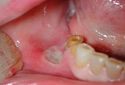

Hamilelik süreci, kadınların fiziksel ve duygusal sağlıkları üzerinde önemli etkiler yaratabilen karmaşık bir dönemdir. Bu dönemde, bazı kadınlar çeşitli sağlık sorunları ile karşılaşabilir. Bu makalede, hamilelikte damak yarası (yarık damak) tedavisinin önemi, nedenleri ve tedavi yöntemleri ele alınacaktır. Damak Yarası Nedir?Damak yarası, doğuştan gelen bir durumdur ve genellikle fetal gelişim sırasında damak bölgesinde meydana gelen anormalliklerden kaynaklanır. Bu durum, damak yapısının tam olarak gelişmemesi nedeniyle ortaya çıkar ve genellikle üst damağın ortasında bir yarık şeklinde görülür. Hamilelikte Damak Yarası NedenleriDamak yarasının oluşumunda çeşitli faktörler etkili olabilir. Bu faktörler arasında genetik, çevresel ve beslenme ile ilgili unsurlar yer almaktadır.

Hamilelikte Damak Yarası BelirtileriDamak yarası, doğumdan önce belirti vermeyebilir. Ancak doğum sonrası bebekte görülen bazı belirtiler, bu durumun varlığını gösterebilir.

Damak Yarası Tedavi YöntemleriDamak yarasının tedavisi genellikle multidisipliner bir yaklaşım gerektirir. Aşağıda tedavi yöntemleri sıralanmıştır: